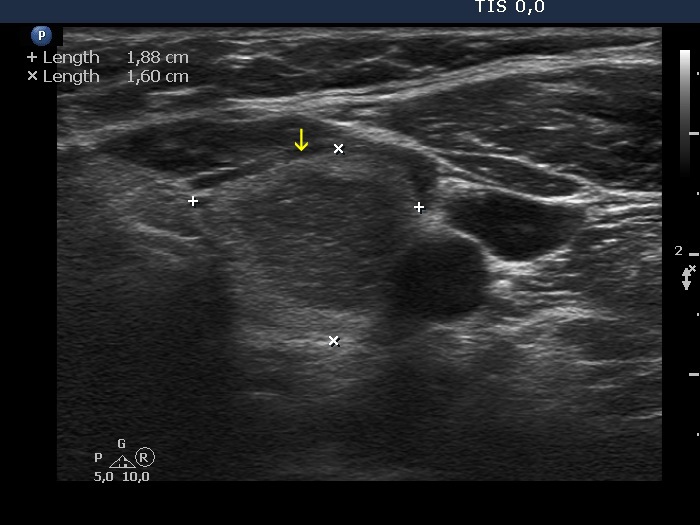

The borders of the nodule - case 2056 (ultrasonographic picture 1b)

Left lobe, transverse scan. There is a protrusion in the ventral part of the nodule. While in the still image it seems to be clearly a pathological lobulation, the situation in the video is equivocal.